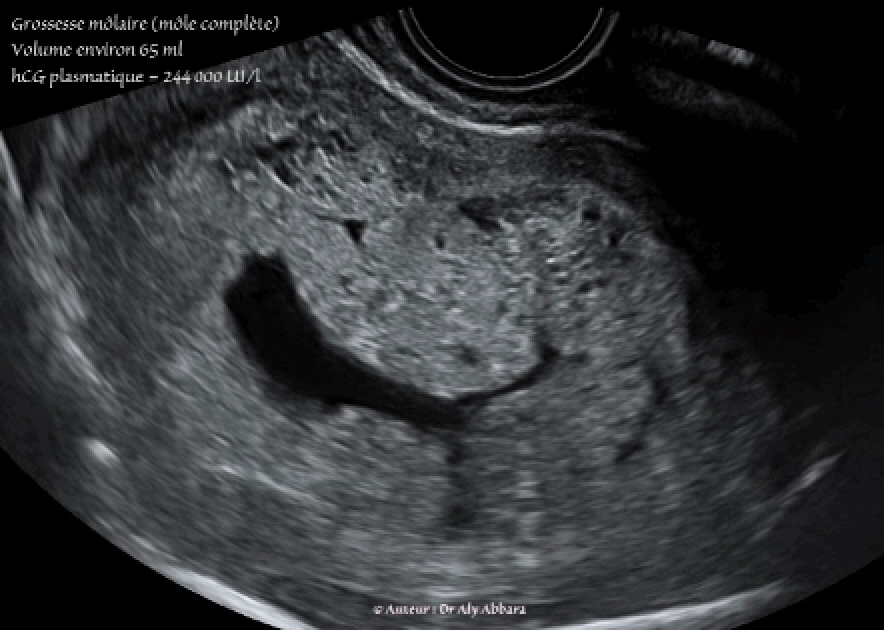

Images échographiques animées montrant l'aspect ultrasonique d'une grossesse môlaire de type môle complète :

I- Une cavité utérine occupée par une structure tissulaire, hétéro-échogène, plutôt vésiculaire .

II- Aucun élément anatomique embryonnaire ou fœtal reconnaissable

III- Pas de vésicule vitelline

IV- Pas de cavité amniotique, par contre la cavité individualisable sur certaines de ces images correspondent à la persistance de la cavité cœlomique (cœlome externe).

Le taux de β-hCG plasmatique le jour de la réalisation de ces images était égal à 244 000 UI/l.